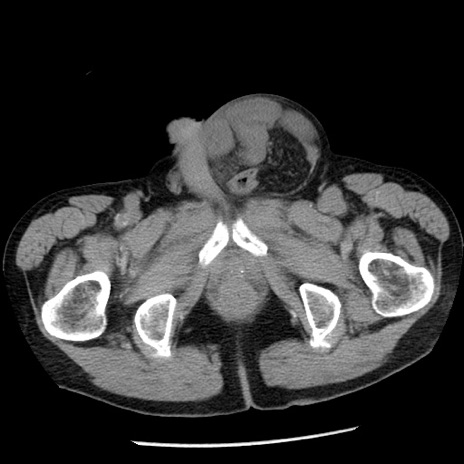

冠状断像

症例26(横断像)

【症例】80歳代男性

【主訴】嘔吐

【現病歴】昨晩2回嘔吐あり、今朝になっても嘔吐あり。来院。

【既往歴】胃潰瘍

【身体所見】意識清明、BT 37.6℃、BP 166/95mmHg、HR 100bpm、SpO2 97%、腹部:平坦・軟、腸蠕動音聴取良好、圧痛なし。

【データ】WBC 21900、CRP 1.46